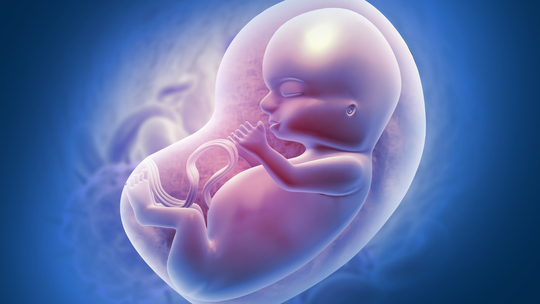

Why Babies Grow in Spurts Instead of a Straight Line Inside the WombOnce you get pregnant, your baby’s growth doesn’t always happen in a consistent manner. Rather, they grow in spurts, periods of rapid development followed by slower phases. This is a usual pattern and crucial for healthy development. Knowing why babies follow such a growth pattern during pregnancy can make you feel calmer during ultrasounds. It also helps you understand what to expect about your baby’s size and weight. It can also assist you in taking better care of yourself, both physically and emotionally.